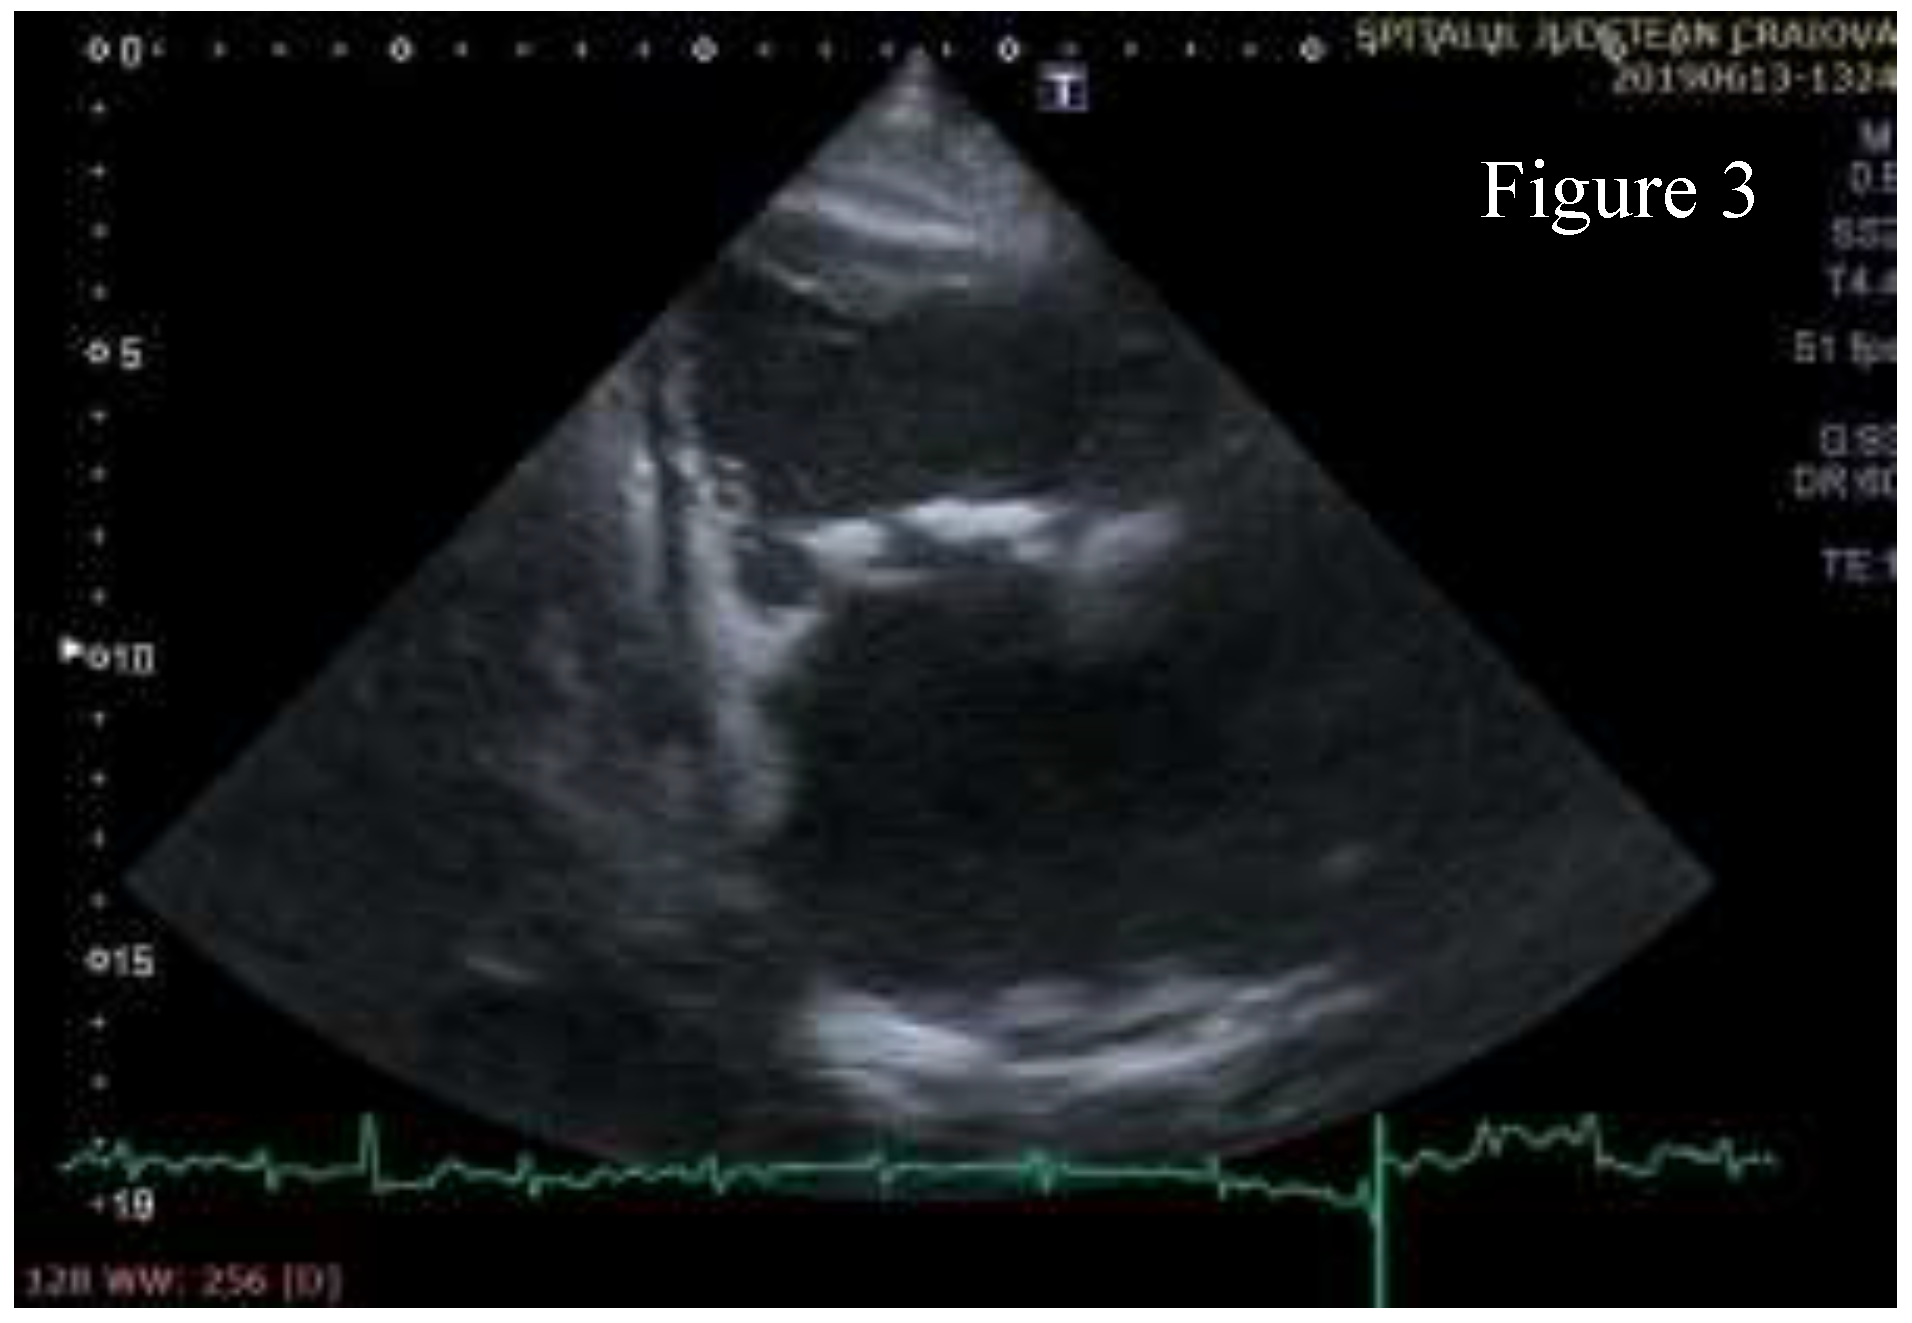

Transthoracic echocardiography (TTE) showed significant structural changes in the tricuspid valve. Anterior and posterior cusps were thickened, calcified, and had restricted motion. Subvalvular chords were thickened. Structural changes caused severe regurgitation (effective regurgitant orifice area= 0.57 cm2, regurgitant volume= 45 ml) and moderate stenosis (high diastolic gradient of 13/6 mmHg which contributed to the high inflow accompanying severe regurgitation). Right chambers were dilated with right ventricle longitudinal systolic dysfunction (TAPSE= 16mm, S’value = 10 cm/s) and with dilated inferior vena cava indicating increased pressure in the right atrium. These aspects are shown in Figure 1, Figure 2, Figure 3, Figure 4, Figure 5.

Figure 3.

Right ventricular inflow view- the anterior and posterior cusps of the tricuspid valve have massive calcifications.